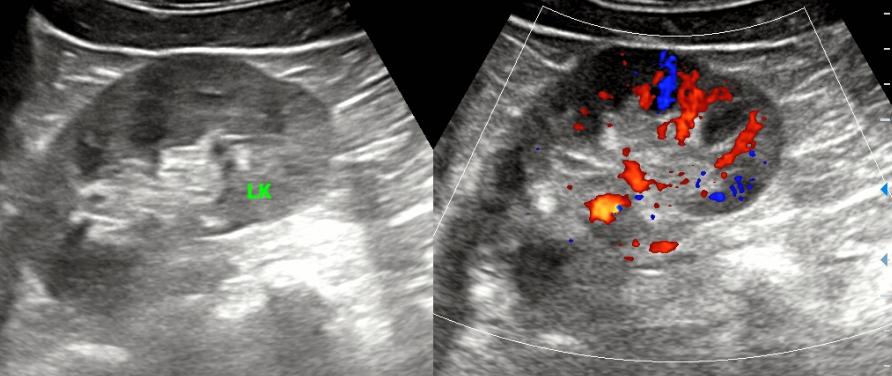

先摆平气体干扰不重的肾脏,没有慢性结石。

那极有可能就是胆囊了,但是胆囊颈部有迷雾包绕,我已经换了好几个体位了,就连坐位都试过了,还是看不清。。。。